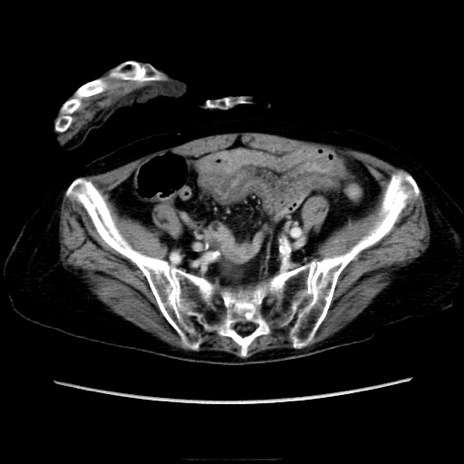

症例40(横断像)

【症例】90歳代女性

【主訴】腹痛・嘔吐

【現病歴】 食欲低下、嘔吐があり昨日他院受診。肺炎と診断され入院となる。入院後より腹部全体に圧痛あり。胃管留置され経過みていたが、症状持続するため、

当院転院となる。

【既往歴】胸椎圧迫骨折、胆石症

【身体所見】腹部:中央に激痛あり、圧痛あり、反跳痛不明

【データ】WBC 17100、CRP 18.82

冠状断像